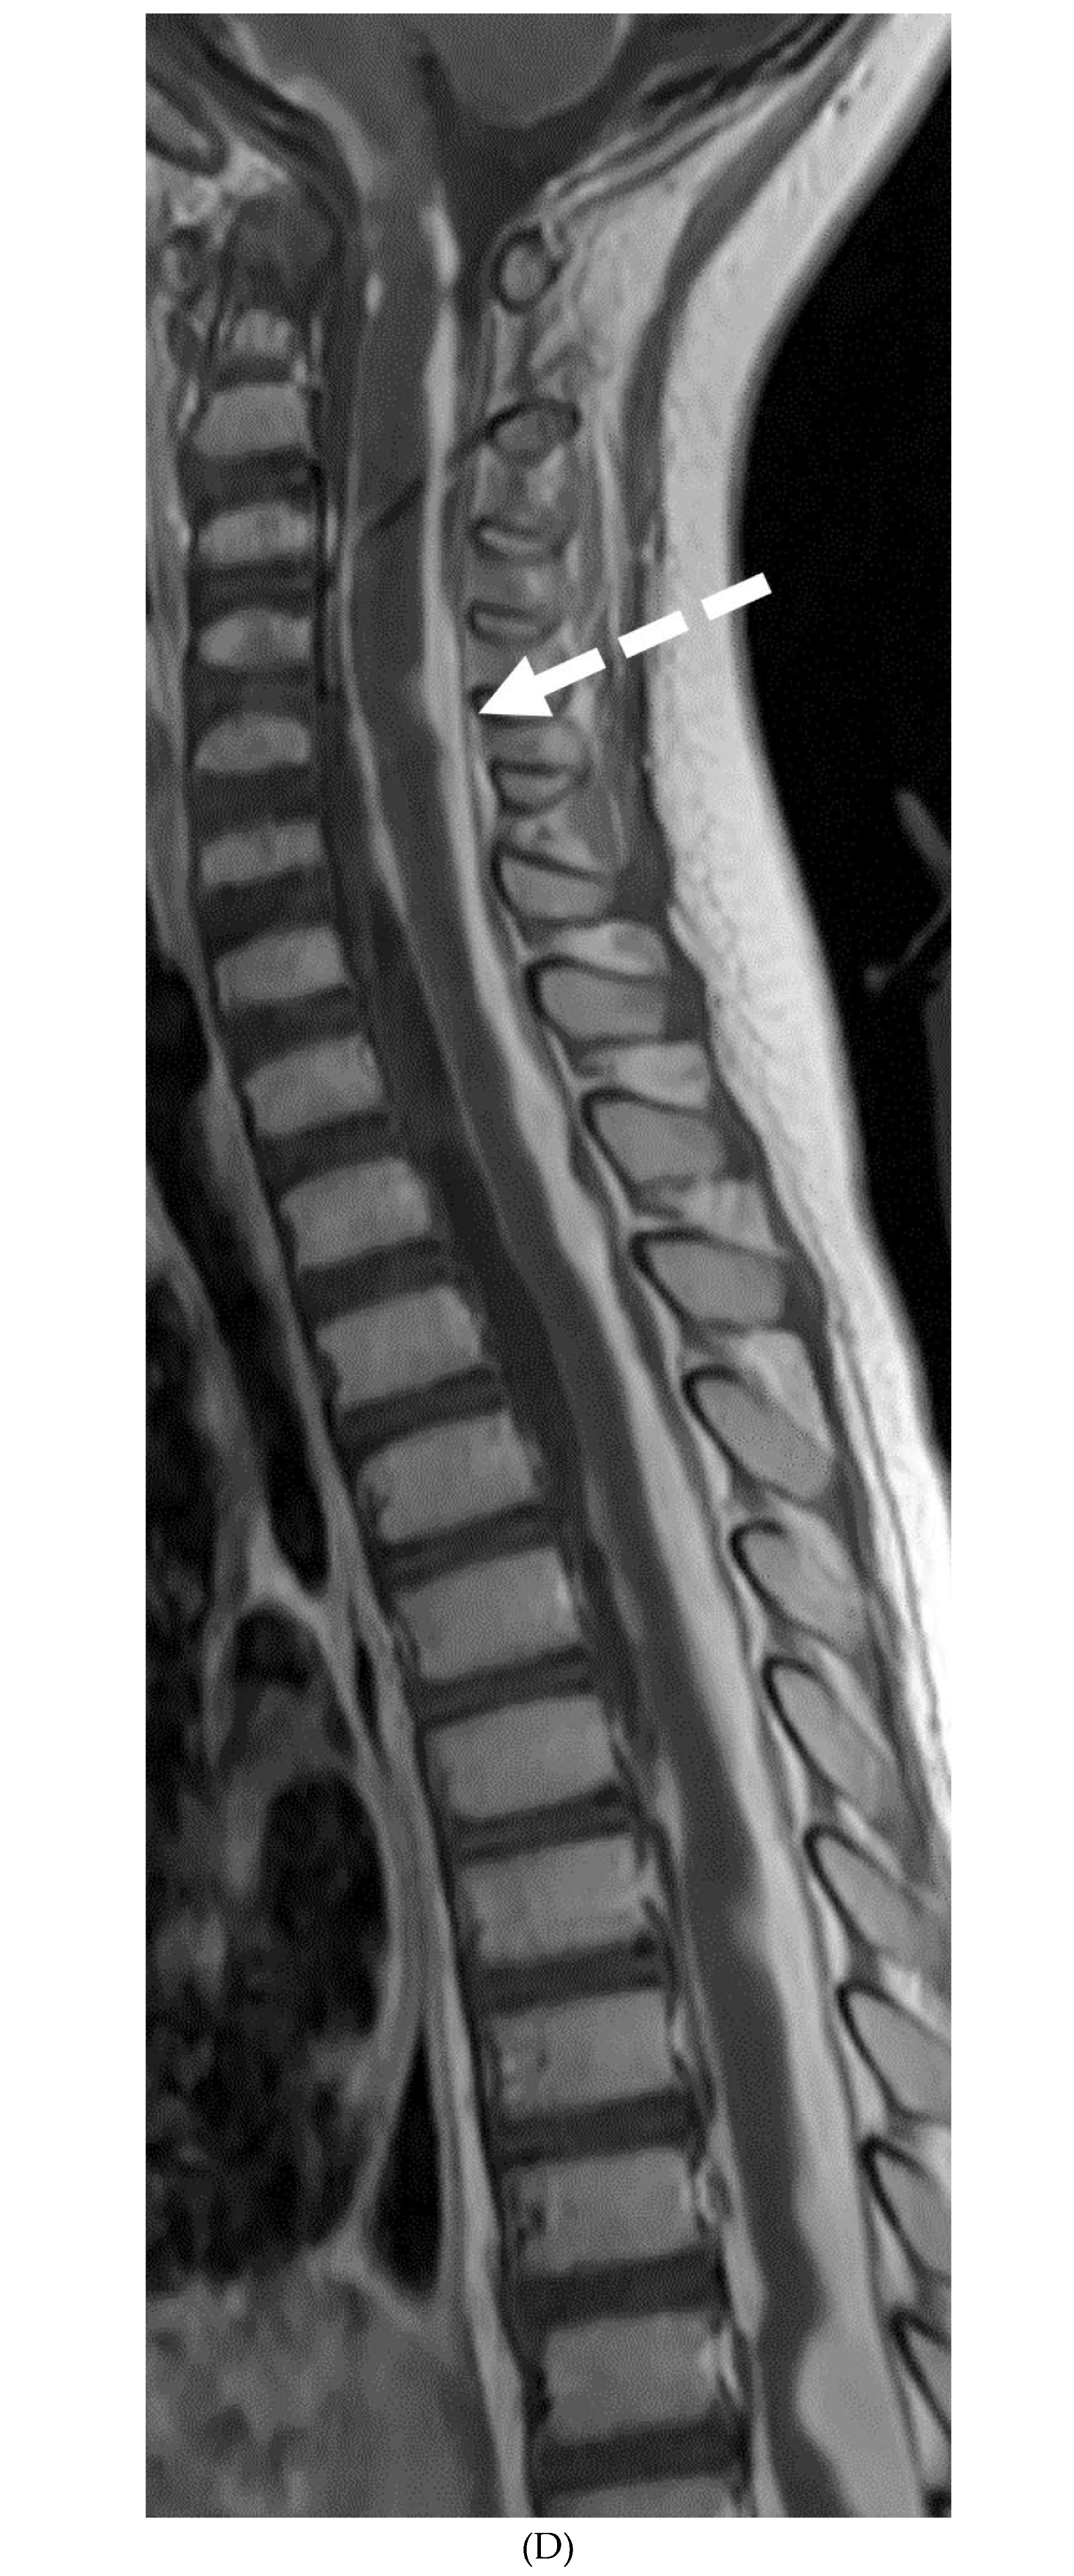

GUILLAIN BARRE SYNDROME

- Alkan O, Yildirim T, Tokmak N, Tan M. Spinal MRI findings of guillain-barré syndrome. J Radiol Case Rep. 2009;3(3):25-8. Epub 2009 Mar 1. PMID: 22470650; PMCID: PMC3303301. [CrossRef]

- Byun WM, Park WK, Park BH, Ahn SH, Hwang MS, Chang JC. Guillain-Barré syndrome: MR imaging findings of the spine in eight patients. Radiology. 1998 Jul;208(1):137-41. PMID: 9646804. [CrossRef]